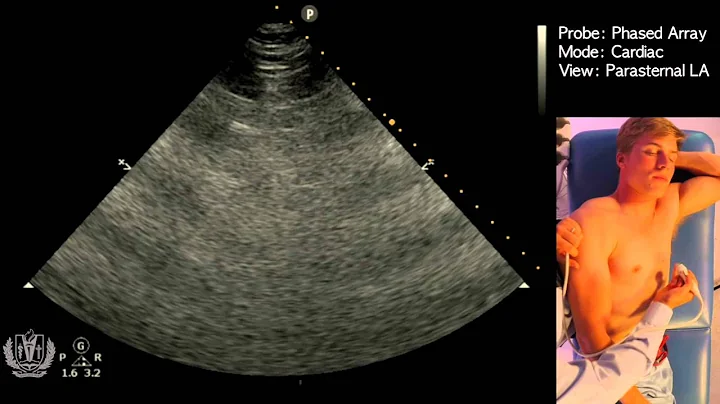

Step by Step instructions on Performing IVC Ultrasound in the Easiest way Possible!